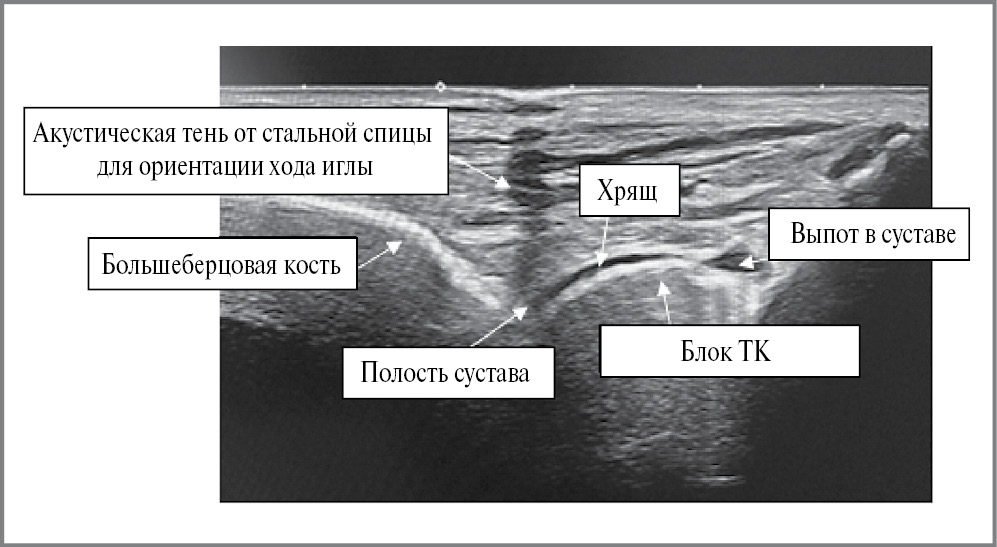

При УЗ-визуализации ориентиром для введения иглы служит пространство между большеберцовой костью и блоком ТК (рис. 6).

Рис. 6. Вид ГСС на экране УЗ-аппарата.

Fig. 6. View of the ankle joint on the screen of the ultrasound machine.